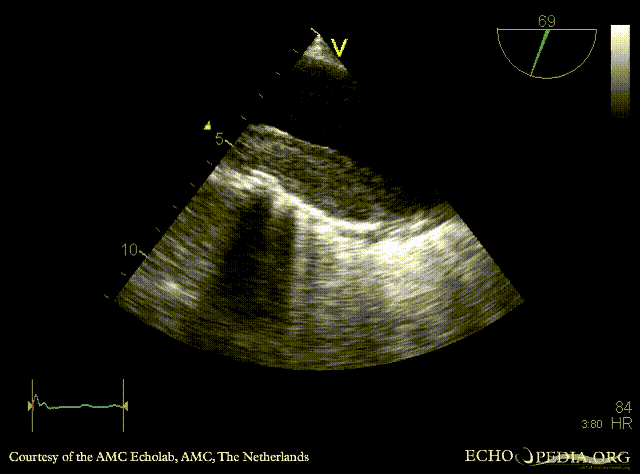

| TEE: dilated aorta | TEE: intramural hematoma of aorta |

| TEE: intramural hematoma of aorta | |